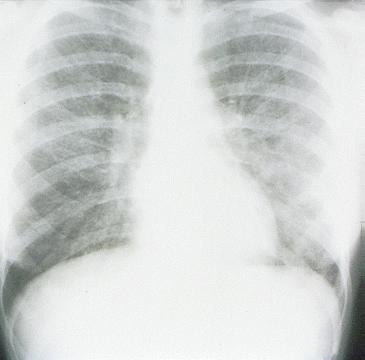

Most common cause of atypical pneumonia (+Dx)